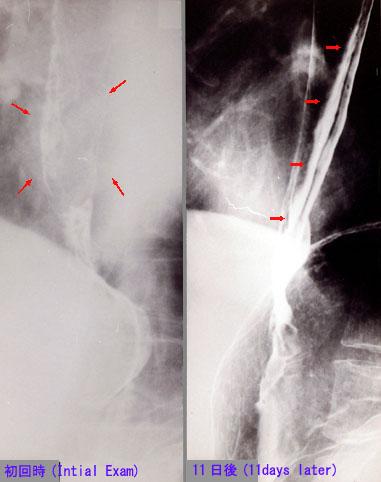

疾病(病理主体)的分类炎症性・溃疡性疾患/其他

部位(按器官分)食道/下

检查方法X线

肿瘤最大直径40以上